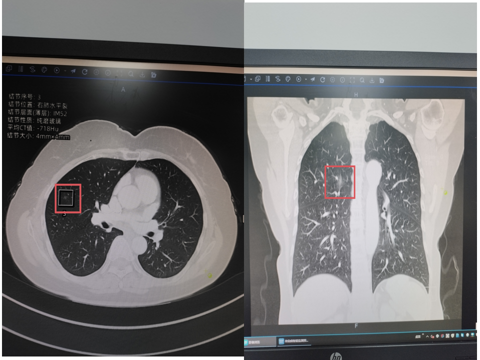

曾有一位女性患者,在 4 个月前于我院进行体检时,胸部 CT 检查发现了右肺结节,随后以 “肺结节” 被收入我科住院治疗。

胸部CT:右肺上叶后段磨玻璃结节(1.4cm*0.6cm)

胸部CT:右中肺结节(直径约0.4cm)

广州医科大学(国家呼吸中心)的崔飞教授仔细阅片后,综合各项因素,考虑该结节为早期肺癌的可能性较大,建议患者接受手术治疗。